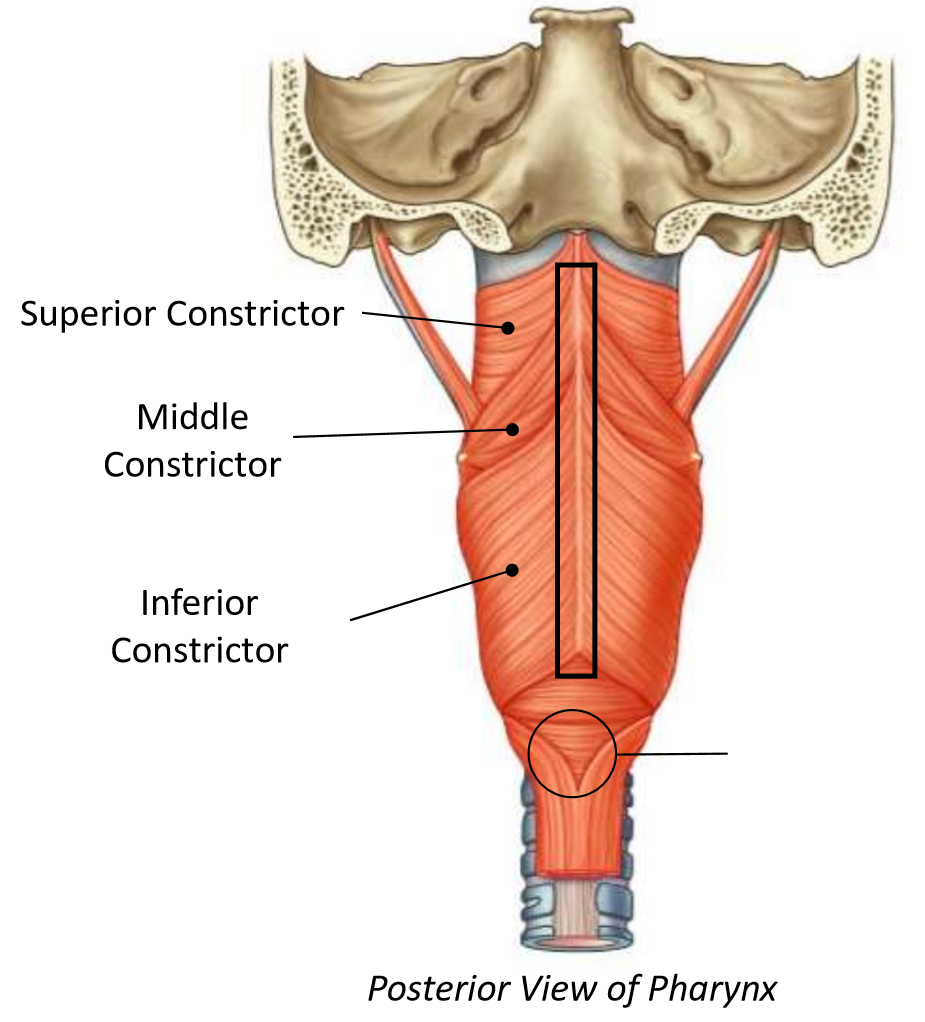

What muscle is this?

superior constrictor

What is the upper border of this muscle?

palatopharyngeal sphincter

What is 1?

pterygomandibular raphe

What is 2?

stylohyoid ligament

What are the attachments of this muscle?

pterygoid hamulus, pterygomandibular raphe, posterior end of mylohyoid line → pharyngeal raphe

What is this muscle?

middle constrictor

What are the attachments of this muscle?

lower stylohyoid ligament, lesser and greater horns of hyoid → pharyngeal raphe

What muscle is this?

inferior constrictor

Which part of the muscle is 1?

thyropharyngeus

Which part of the muscle is 2?

cricopharyngeus

What are the attachments of this muscle?

oblique line of thyroid cartilage, cricothyroid tendon, cricoid cartilage → pharyngeal raphe

What is in the rectangle?

pharyngeal raphe

What is in the circle?

killians dehiscence